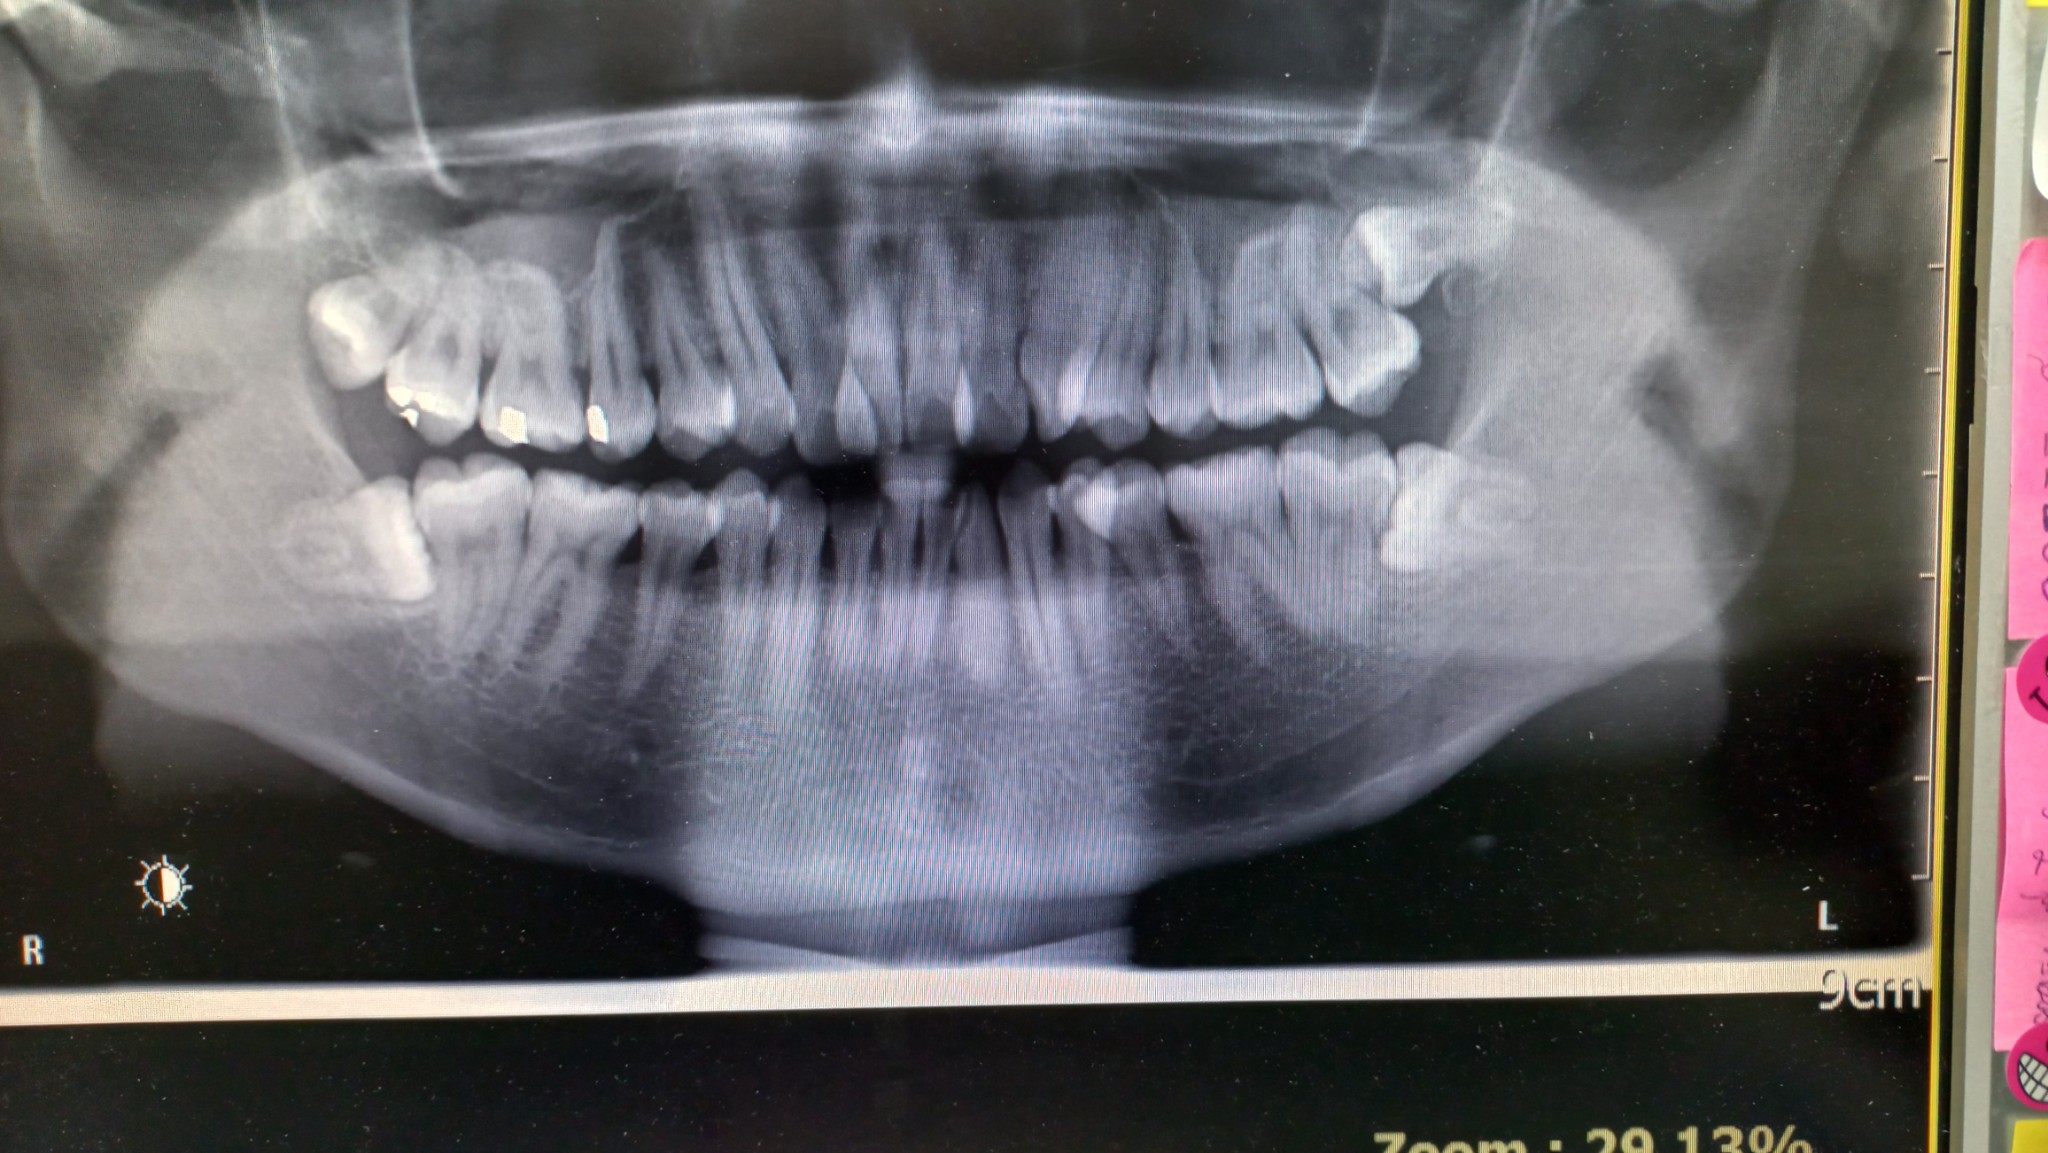

สอบถามหน่อยครับ ตอนนี้ผมมีฟันคุดอยู่ 2 ซี่ ซี่หนึ่งขึ้นเฉียงๆ อีกซี่นอนอยู่โผล่มานิดเดียว หมอแนะนำให้ผ่าออกทั้ง2 พอดีจะถึงคิวแล้ว เลยมาคิดว่าจะผ่าดีหรือยกเลิก เพราะที่ผ่านมาไม่เคยมีอาการอะไร ไม่ปวดไม่ผุไม่เสียว ใช้ชีวิตปกติ อยากได้ความเห็นทั้งคนที่ตัดสินใจผ่า หรือคนที่ปล่อยเอาไว้ รวมถึงถ้ามีทันตแพทย์มาอ่าน ช่วยตอบด้วยก็ได้ครับ (มีรูป)